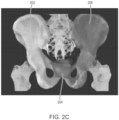

• the output of the Localization CNN is a coarse segmentation, e.g., represented via a first segmentation mask set, that classifies voxels of the preprocessed CT image as belonging to one of four categories, three representing particular tissue regions: (i) a sacrum and coccyx, (ii) a left hip bone, (iii) a right hip bone, and a fourth category, (iv) background (e.g., everything else).

• Each channel corresponds to a particular classification category - (i) sacrum and coccyx, (ii) left hip bone, (iii) right hip bone, and (iv) background.

• a bounding box that identifies an initial VOI may be determined from the first segmentation mask set as a smallest box (e.g., rectangular volume) that comprises all voxels labeled as belonging to categories (i) - (iii). Coordinates identifying the bounding box (e.g., coordinates of opposite corners of a rectangular volume corresponding to the bounding box) are determined and output as crop endpoints.

• a second machine learning module also referred to as a base Single Segmentation Machine 1208 (SingleSegMachine (base) in FIG. 12 ) performs a high-resolution segmentation of a CT image to identify a prostate volume corresponding to a prostate of the subject, along with additional tissue volumes corresponding to specific tissue regions, such as left and right gluteal muscles, a rectum, a bladder, a sacrum and coccyx, and left and right hip bones.

• a subset of connected components of the prostate segmentation mask is considered. The subset comprises only components that (i) have a center of mass lying in between the hip bones' centers of mass in a left-right direction of an axial plane (x direction) and (ii) lie within a bounding box defined so that the left and right hip bones are just contained.